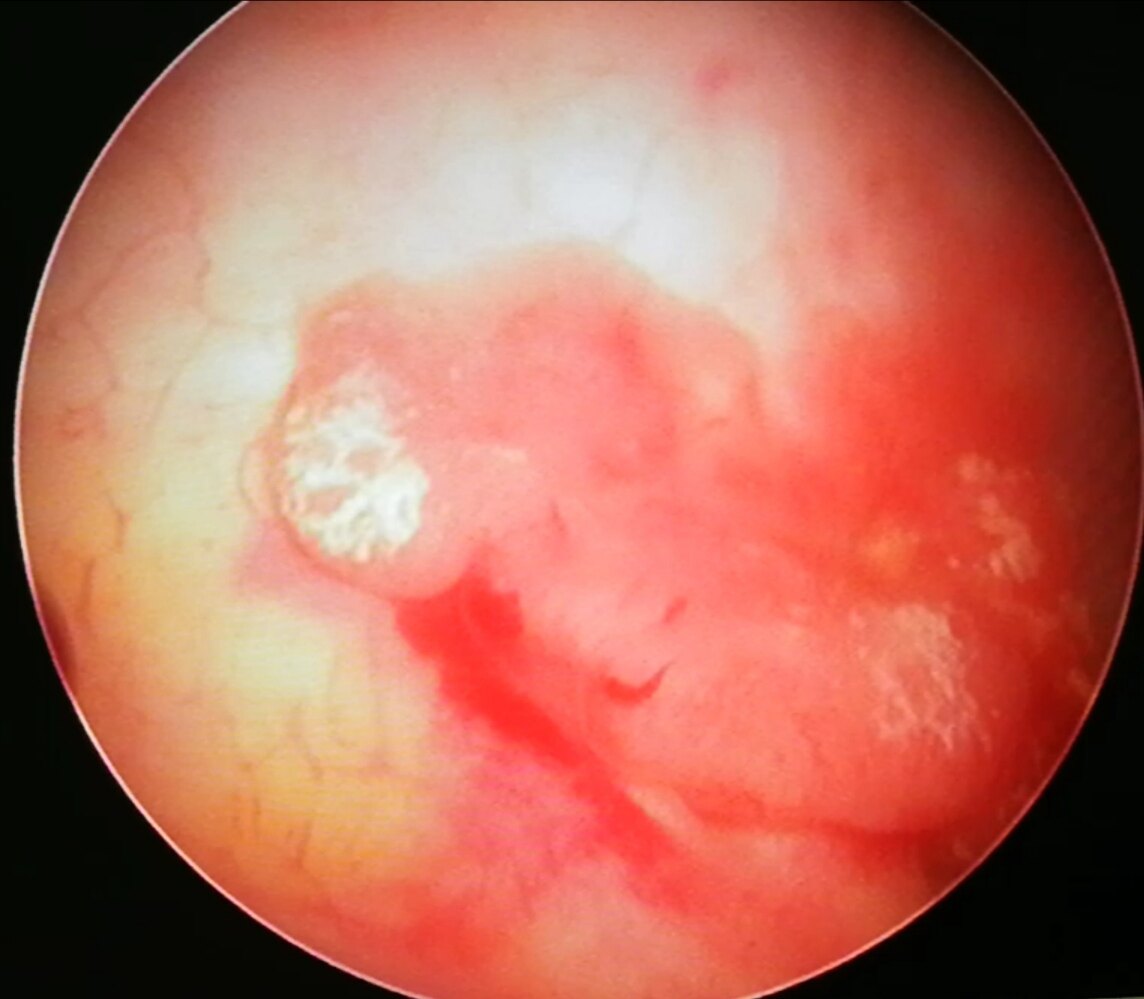

膀胱癌是发生于膀胱粘膜的恶性肿瘤,按细胞来源,病理上可以分为尿路上皮癌、鳞状细胞癌、腺癌和其它一些少见的肿瘤。其中尿路上皮癌最多见占90%,鳞癌约3-7%,腺癌约2%。通常我们所说的膀胱癌通常是膀胱尿路上皮癌。

膀胱粘膜是尿路上皮组成的,实际上肾盂与输尿管、膀胱、部分后尿道等都是尿路上皮覆盖的,所以说从广义上来说,尿路上皮存在的地方都有可能发生癌症,肾盂癌、输尿管癌、膀胱癌和后尿道的一些肿瘤都是同源性的,都叫尿路上皮癌,但是在这些部位当中,膀胱尿路上皮癌是最多见的。膀胱癌是男性泌尿生殖系统恶性肿瘤发病率是最高的,排名第一位的一个恶性肿瘤。